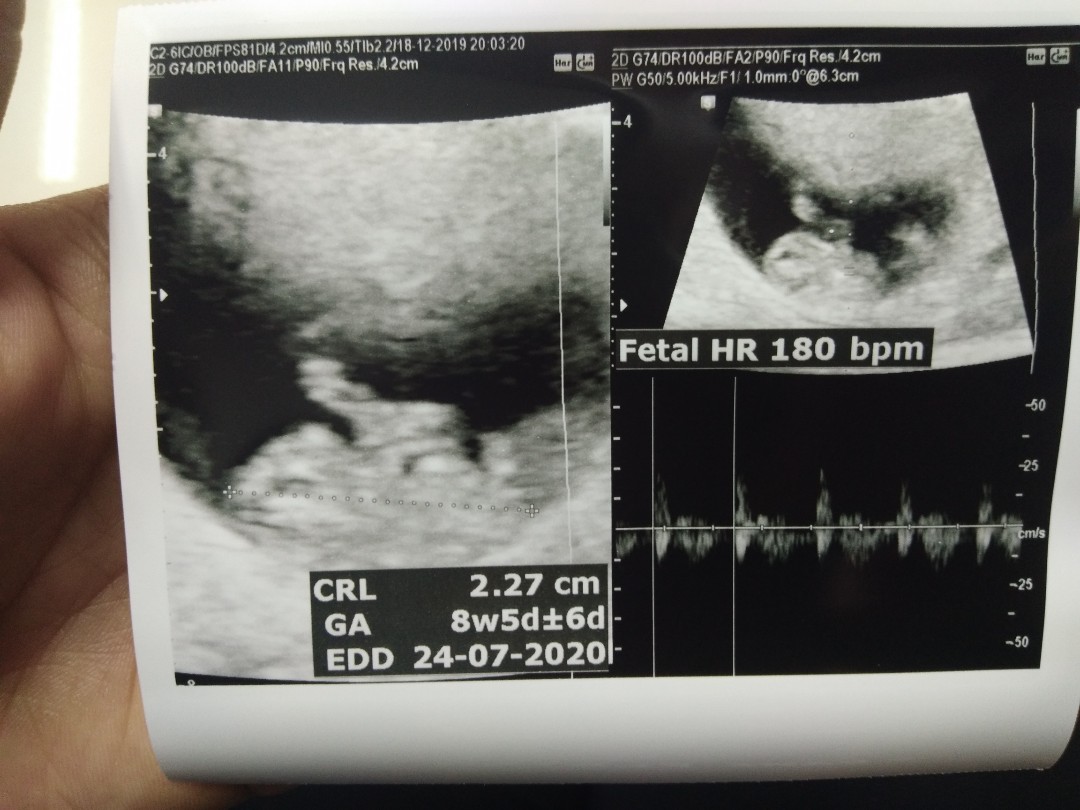

8 Week ค่ะ